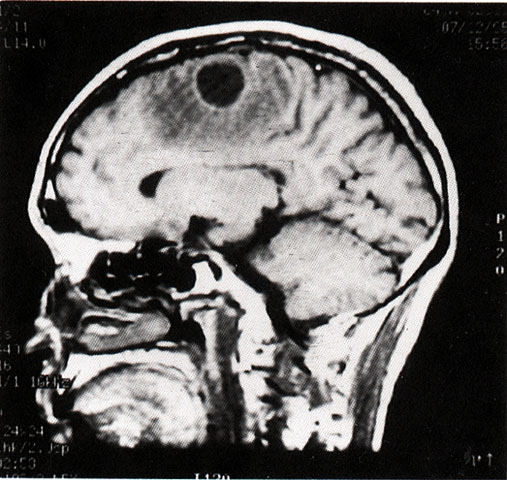

FH1047 脑脓肿(MRI)

光盘检索编码 FH1047  函授作业图编号 1047

图  名 脑脓肿(MRI)